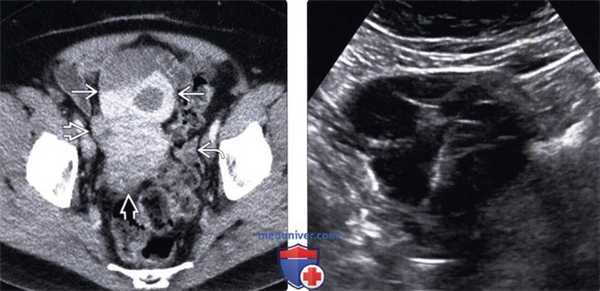

3. КТ при метастазах в яичники и опухоли Крукенберга:

• Обзорная КТ:

о Метастатические опухоли яичников часто имеют плотность соединительной ткани, однако могут визуализироваться кистозные или некротические области со сниженным затуханием сигнала

• КТ с контрастированием:

о Часто неоднородное контрастирование солидных компонентов

о Отсутствие контрастирования кистозных и некротических очагов

о Метастатический колоректальный рак может иметь вид многокамерного кистозного образования с участками «матового стекла»:

- Контрастирование очагов варьирует

- Имитирует первичный муцинозный рак яичников

(Левый) На аксиальном КТ срезе с контрастированием с целью рестадирования рака ободочной кишки у женщины 61 года визуализируется гетерогенное новообразование придатков кпереди от матки. Опухоль содержит гиперденсивные очаги, указывающие на геморрагическое содержимое. Обратите внимание на неизмененный левый яичник

(Правый) На трансабдоминальном УЗ срезе у этой же па циентки визуализируется многокамерная киста без выраженного солидного компонента. Хотя данные визуализации указывают на геморрагическую кисту, ее наличие нехарактерно для постменопаузального периода.